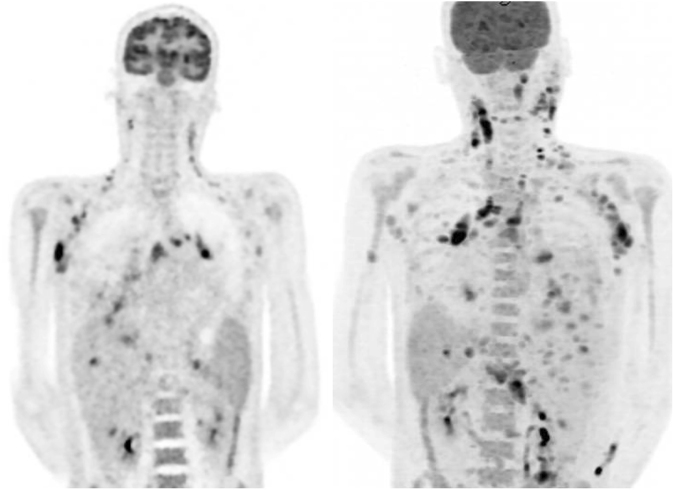

干扰素-γ (IFN-γ)自身抗体综合征是一种新兴的临床实体,与播散性非结核分枝杆菌感染(dNTM)有关,特别是在健康年轻人中,这一人群以前未被认为具有特别的风险。一名29岁东南亚男子在一艘国际货船上工作时出现数周的发热、咳嗽、淋巴结病和体质症状,病情迅速恶化并出现败血症样综合征。淋巴结和痰培养最终诊断为dNTM感染,同时生长有仙桃分枝杆菌和脓肿分枝杆菌。他开始使用利妥昔单抗和联合抗分枝杆菌治疗,临床反应良好。该病例突出了dNTM患者在IFN-γ自身抗体背景下面临的一些困难,特别是诊断延迟,以及缺乏围绕最佳管理的证据基础。需要对长期结果和治疗进行进一步研究,并提高临床医生的认识。

Interferon-gamma (IFN-γ) autoantibody syndrome is an emerging clinical entity that has been associated with disseminated non-tuberculous mycobacterial infection (dNTM) particularly in healthy young people, a population not previously thought to be at particular risk. A 29-year-old South-East Asian man presented with several weeks of fever, cough, lymphadenopathy, and constitutional symptoms while working on an international cargo ship, deteriorating rapidly with a sepsis-like syndrome. Eventually lymph node and sputum cultures revealed a diagnosis of dNTM infection with growth of both Mycobacterium persicum and Mycobacterium abscessus. He was commenced on rituximab as well as combination anti-mycobacterial therapy with good clinical response. This case highlights some of the difficulties faced by patients with dNTM in the context of IFN-γ autoantibodies, particularly delayed diagnosis, and lack of evidence base surrounding optimal management. Further research into long-term outcomes and treatment is required as well as increased awareness among clinicians.